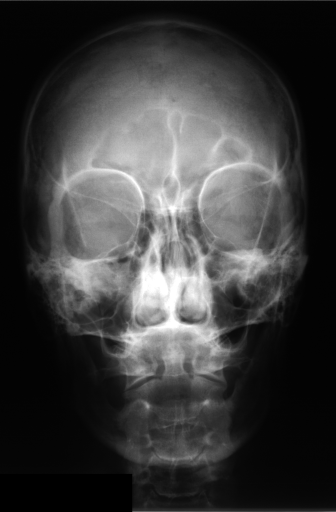

Saliency maps of all training images are generated and averaged to calculate a saliency template (Algorithm 2). Figure 1 shows three images, their saliency maps, and the saliency template created by averaging all saliency maps. The average of saliency maps is first calculated internally within each class, then the average is taken across all classes.

The salient, less salient and not salient areas are defined for training data by dividing images to sub-blocks. Then, based on the saliency template, the folding is applied. The new images with reduced area can now be used for local pattern analysis.